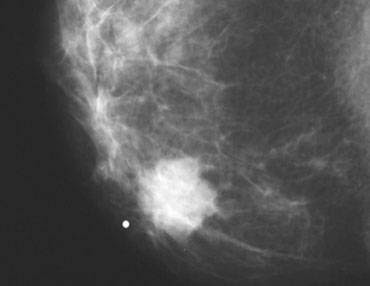

Achados:

- Nódulo com forma irregular e contornos espiculados;

- Microcalcificações pleomórficas, lineares ou arboriformes, com distribuição linear/segmentar.